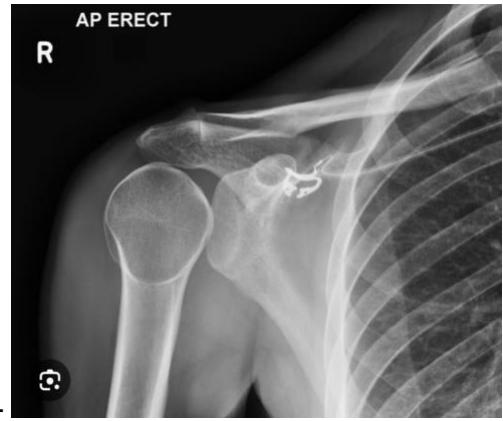

Anterior Shoulder Dislocation

What is the diagnosis shown in the image?

- Anterior Shoulder Dislocation

What is the most common complication of anterior shoulder dislocation?

- Axillary nerve injury